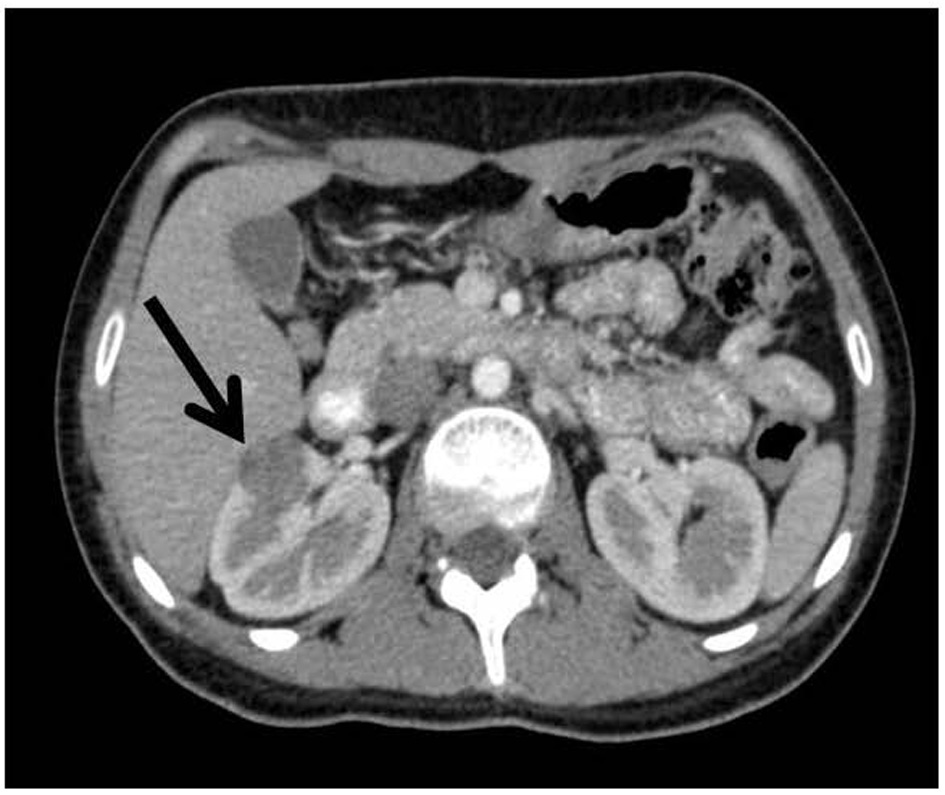

We present the case of a 19-year-old female without a family history of hypertension. She had generalized headache 7 months prior to her admission. Physical examination was positive for hypertension (170/120) and asymptomatic hypokalemia (2.6 mEq/L). She had preserved renal function with creatinine of 0.57 mg/dL, normal urinalysis, sodium of 138 mEq/L, serum potassium of 2.6 mEq/L, Cl of 108 mEq/L, 24-h urine electrolytes of potassium of 57.96 mmol, sodium of 115.20 mmol, chloride of 88.2 mmol, and normal metanephrines. She demonstrated a negative immune profile, cortisol of 10 μg/dL (5 - 25 morning, 2.5 - 12.5 afternoon), aldosterone of 95 pg/mL (supine 10 - 160, standing 40 - 310), renin of 294.4 μUL/mL (supine 2.8 - 39.9, standing 4.4 - 46.1) with balanced metabolic alkalosis (pH 7.40, pCO2 46, HCO3 27.9). Abdominal computed tomography (CT) reported preserved kidney size with a hypodense image in the cortex of the mid-region of the right kidney of 20.9 × 14.5 mm, which was not contrast enhanced (Fig. 1). The patient underwent right laparoscopic tumor removal with a definitive pathological diagnosis with positive immunohistochemistry for CD117 and actin (Fig. 2, 3), respectively, and negative for cytokeratin, desmin, S-100 protein and chromogranin. At the time we did not have CD34 marker but, based on the clinical, biochemical and imaging behavior, diagnosis JGCT was made. On the day following surgery, the patient did not require continuation of antihypertensives. Serum potassium returned to normal levels and metabolic alkalosis resolved.

![]() Click for large image | Figure 1. Contrast tomography of the abdomen that reports preserved kidney size with a hypodense image in the cortical region of the right kidney of 20.9 × 14.5 mm that is not reinforced with contrast. |

Renal ultrasound shows a hypoechoic mass; however, it is useful to make a differential diagnosis especially in malignant lesions. CT is therefore recommended where those malignant lesions acquire an important enhancement. On tomography, reninoma appears as a well-circumscribed hypodense cortical mass that does not enhance in the arterial phase despite its profuse vascularity. This is probably due to the vasoconstriction induced by the renin. Without a doubt, definitive diagnosis is made immunohistochemically and the clinical behavior on tumor resection, although 10% of patients may persist with hypertension due to angiopathic damage [4].